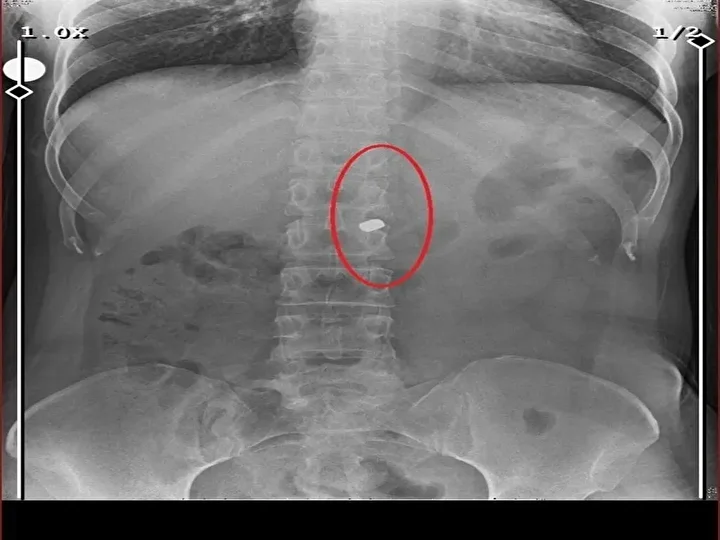

Osmangazi ilçesi Küplüpınar Mahallesi'nde 2023 Haziran ayında meydana gelen olayda; İlyas S., mahalleden arkadaşı Recep Özaslan'ı, Alzheimer hastası annesi A.S. ve sevgilisi Fatma O. ile birlikte yaşadığı eve çağırdı. İddiaya göre; uyuşturucu etkisinde olan İlyas S., sevgilisiyle ilişkisi olduğunu düşündüğü Özaslan'ı tabancayla vurdu ardından da 'acı çekmesin' diye 2 kez daha ateş etti. Özaslan, beline ve göğsüne isabet eden kurşunlarla olay yerinde hayatını kaybetti.

İlyas S., sevgilisi Fatma O.'yu da 8 kurşunla vurup, yaraladı. Arkadaşı Özaslan'ın cesedini önce çarşafa sonra da streç filme sarıp bantlayan İlyas S., eczaneden aldığı sargı bezi ve ilaçlarla pansumanını yaptığı sevgilisine yaralı haldeyken 21 gün boyunca cinsel saldırıda bulundu.